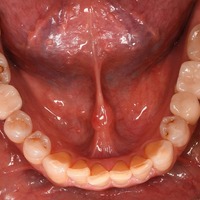

たった一日で何年もなかった歯がよみがえりました!! 昨日、私は大阪の中山隆司先生に即時荷重インプラントをしてもらいました。 上の写真は現在の私の口腔内(下顎)の写真です。 全く腫れておりません。痛みもまったくありません。 向かって、左が奥から3番目の歯、右が奥から2番目。 両側下顎第一大臼歯です。 歯の色…